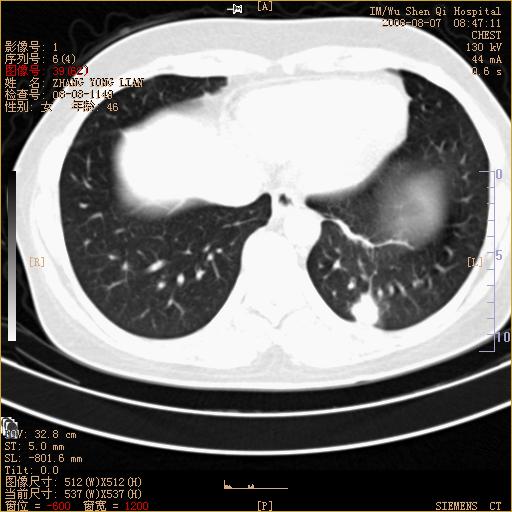

标题: CT15050:女,46岁,咳嗽胸痛一月余 [打印本页]

纵隔窗没发全,左下肺近胸膜处结节。有长毛刺,纵隔淋巴结增大,不排除恶性病变。

考虑肺癌

考虑左肺下叶后基底段周围型肺癌伴纵隔淋巴结转移可能性大。

左下肺ca并纵隔及左肺门区淋巴结转移。

脾脏低密度结节转移不排除。

1)考虑左肺下叶后基底段周围型肺癌伴纵隔淋巴结转移。2)脾内低密度灶,性质待定;不排除转移瘤可能。

考虑左肺下叶后基底段周围型肺癌伴纵隔及肺门淋巴转移。